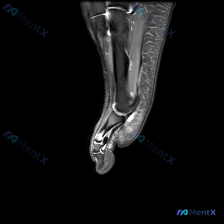

看到一份踝关节MRI的读片资料,整理了完整的分析和鉴别思路分享给大家。 病例核心影像信息 这是踝关节上方水平的轴位T2序列MRI: 1. 解剖层面:显示踝穴上方的胫骨远端干骺端、腓骨远端,可清晰识别跟腱、胫骨后肌腱、趾长屈肌腱、踇长屈肌腱、腓骨长短肌腱等结构 2. 核心阳性发现:内踝后方胫骨后肌腱的...